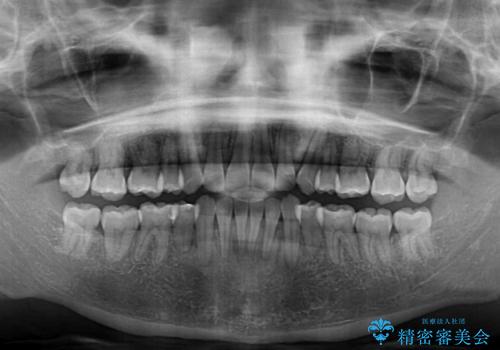

上下顎ともに前突した歯列であったので、上下ともに左右の第1小臼歯4本を抜歯し、ワイヤー装置にて矯正治療を行うこととしました。

抜歯スペースに前歯を移動させることで歯の突出感が改善され、非常に唇が閉じやすい仕上がりとなりました。